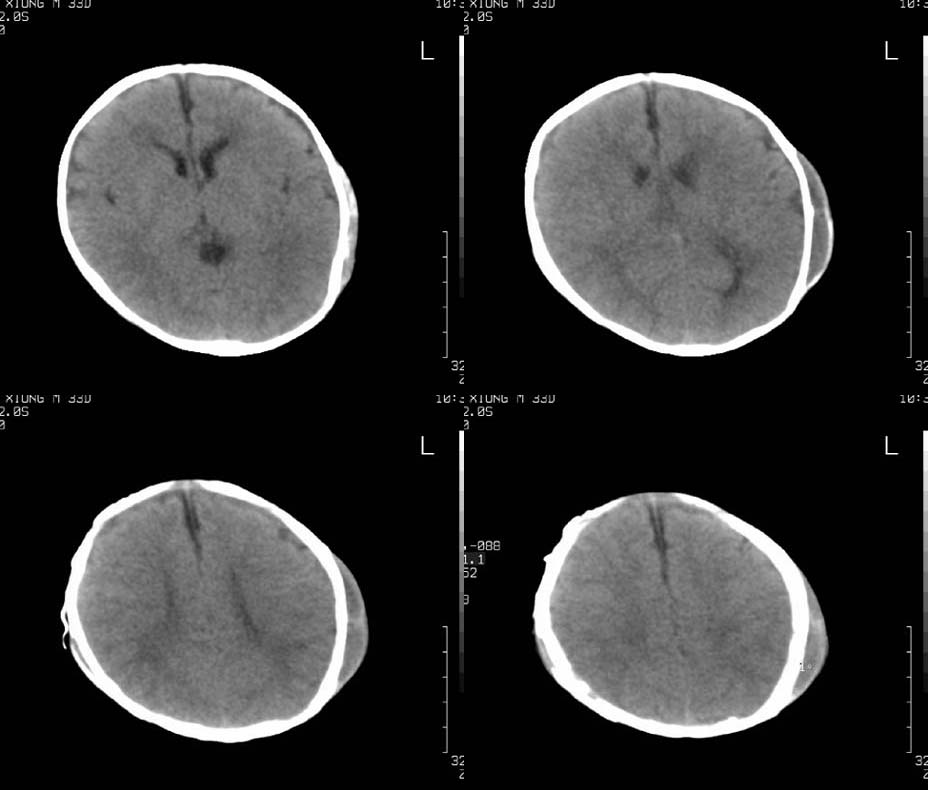

患儿,男,30天。出生时即发现两侧头顶部肿块,触诊似乒乓球样,其余各项检查未见异常。ct扫描:两侧顶骨外侧软组织密度影,ct值约29hu,脑皮质ct值约28.1hu。外缘尚见骨样结构。